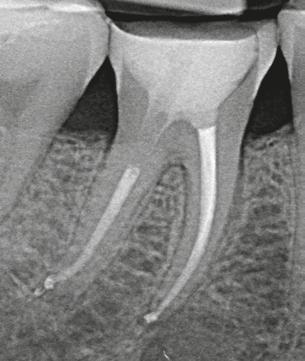

Trattamento canalare ortogrado dell’elemento 46: sagomatura con Absoulte shaper, detersione con Ipoclorito di Sodio e EDTA attivati con Ultrasuoni, otturazione con tecnica della compattazione verticale a caldo della guttaperca.

Caso clinico Dr. Filippo Cardinali Lastra pre-operatoria Lastra post-operatoria